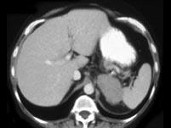

- 单项选择题女,47岁, 满月脸、向心性肥胖伴高血压1月,结合图像, 最可能的诊断是 ( )

A、左肾上腺腺瘤

B、左肾上腺腺癌

C、左肾上腺转移癌

D、左肾上腺嗜铬细胞瘤

E、左肾上腺增生